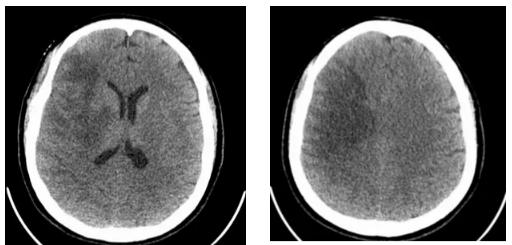

在医疗条件相对有限的高原县城,救治团队克服困难,对患者进行了不间断的严密监测,连续追踪头颅CT影像变化。经过数个日夜的坚守和精心治疗,患者的病情终于出现了转机。至10月22日复查显示,致命的脑疝得到缓解,脑水肿范围显著缩小,患者成功度过了最危险的阶段,病情逐步稳定下来。

此次成功救治,是基层医院危急重症应急处置能力、远程医疗协作效能以及医护人员不畏艰难、永不放弃精神的集中体现。青南支医医师周珉表示:“在高原地区,虽然医疗资源面临挑战,但通过规范的抢救流程、及时的远程会诊支持和团队的紧密协作,我们依然能够创造生命的奇迹,为患者赢得生机。”这场成功的救治不仅挽救了生命,更彰显了高原医务工作者尽心尽力、守护健康的坚定信念。